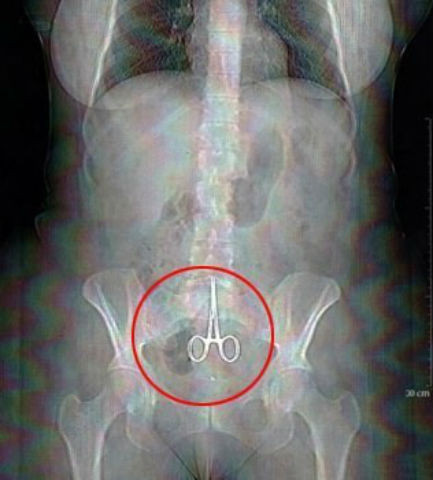

Cô Nicole Haynes đã qua đời bất ngờ sau 1 ca phẫu thuật nội soi ổ bụng đơn giản. Sau đó nhân viên bệnh viện đã phát hiện một đoạn phim ghi lại toàn bộ quá trình phẫu thuật. Nội dung đoạn phim cho thấy, các bác sĩ chịu trách nhiệm về ca mổ đã bỏ quên… kéo trong bụng bệnh nhân và không thực hiện đầy đủ những thao tác cần thiết khi hoàn thành phẫu thuật.